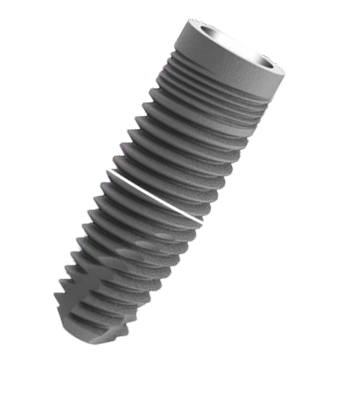

Advanced EV Implant System

Designed for immediate load

with functional Prosthesis.

Shorter Time to Teeth.